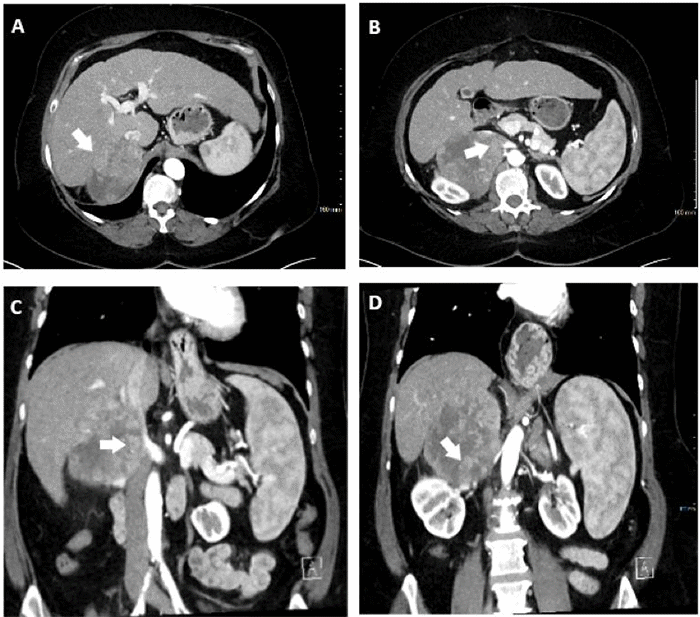

She was referred for surgical evaluation but was lost to follow-up for three months, subsequently presenting with right upper quadrant abdominal discomfort. A triphasic liver CT demonstrated an 11.0 × 9.3 × 7.6 cm (approximately 2 cm growth in 3 months) retrocaval HCC with a long interface with the infrahepatic IVC, inferiorly displacing the right kidney (Figure 1), and an adjacent 2 cm nodule. Staging CT of the chest, abdomen, and pelvis showed no evidence of distant metastasis. The tumor was deemed not favorable for liver-directed therapies and beyond size criteria for liver transplantation. Given the patient’s Child-Pugh A cirrhosis and the tumor’s anatomical resectability, surgical resection was considered, although it was recognized that the procedure would be complex and potentially require en bloc resection of the IVC.

Figure 1. Preoperative Contrast-enhanced CT Imaging. Published with Permission

(A) An 11.0 × 9.7 × 7.1 cm tumor located in the hepatorenal recess of a cirrhotic liver. (B) The tumor, arising from liver segment VII, exhibiting direct contact with the inferior vena cava (arrow); (C) an extensive tumor-vena cava interface, extending superiorly from the hepatic confluence to the renocaval junction and inferiorly to the renal pelvis (D).